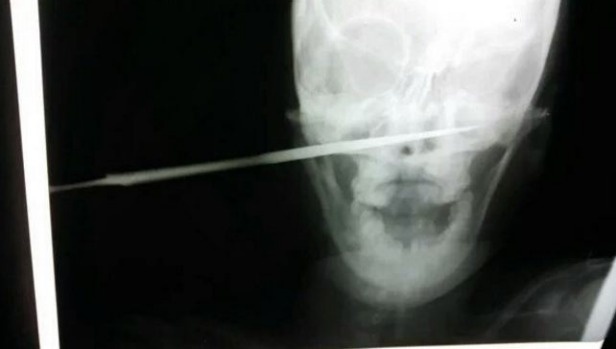

Οι φωτογραφίες της γυναίκας από το το νοσοκομείο που νοσηλεύεται, με την λαβή του μαχαιριού να προεξέχει από το αριστερό της μάγουλο και μιας ακτινογραφίας που να δείχνει την λεπίδα να διαπερνά από την μια μεριά του κρανίου της στην άλλη, διαδόθηκαν στα μέσα κοινωνικής δικτύωσης, με αναρτήσεις που έκαναν εκκλήσεις για απονομή δικαιοσύνης στην υπόθεση (#JusticeforFatuma).